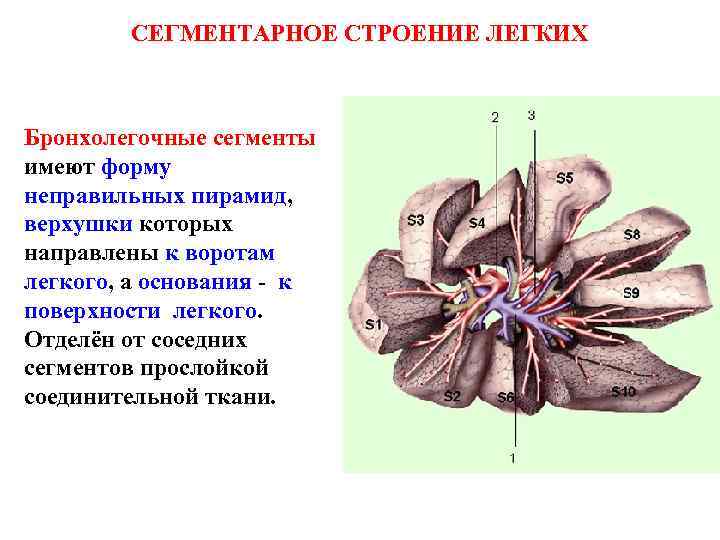

Анатомические изображения сегментов легких различных животных

Раздел: Другие животные